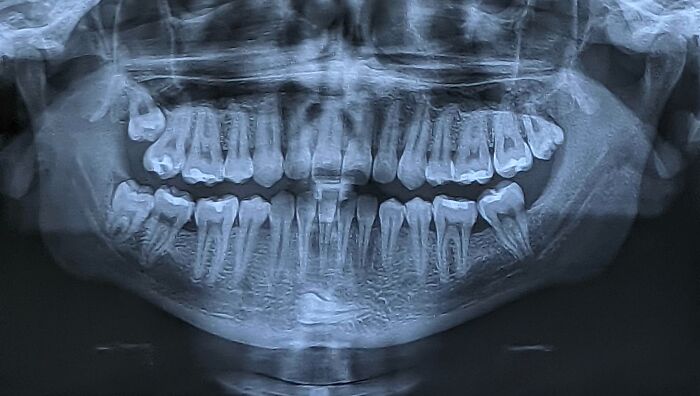

There's A Tooth In My Chin

I have one just like that but didn't know until dental x-rays began to wrap around the front. Doc looked at me and said, "You have a supernumerary tooth!" Me (decoding) - "You mean 'extra?'" "Yes, but we charge more for supernumerary."